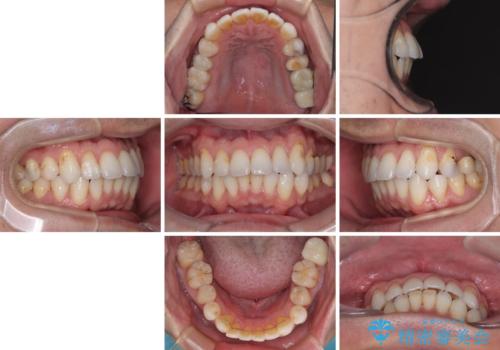

根管治療の途中で、矯正治療の後戻りが気になるとのことで、下顎前歯の叢生を改善するためにマウスピース矯正を並行して行いました。

目立っていた銀歯がなくなり、患者様には大変満足していただけました。